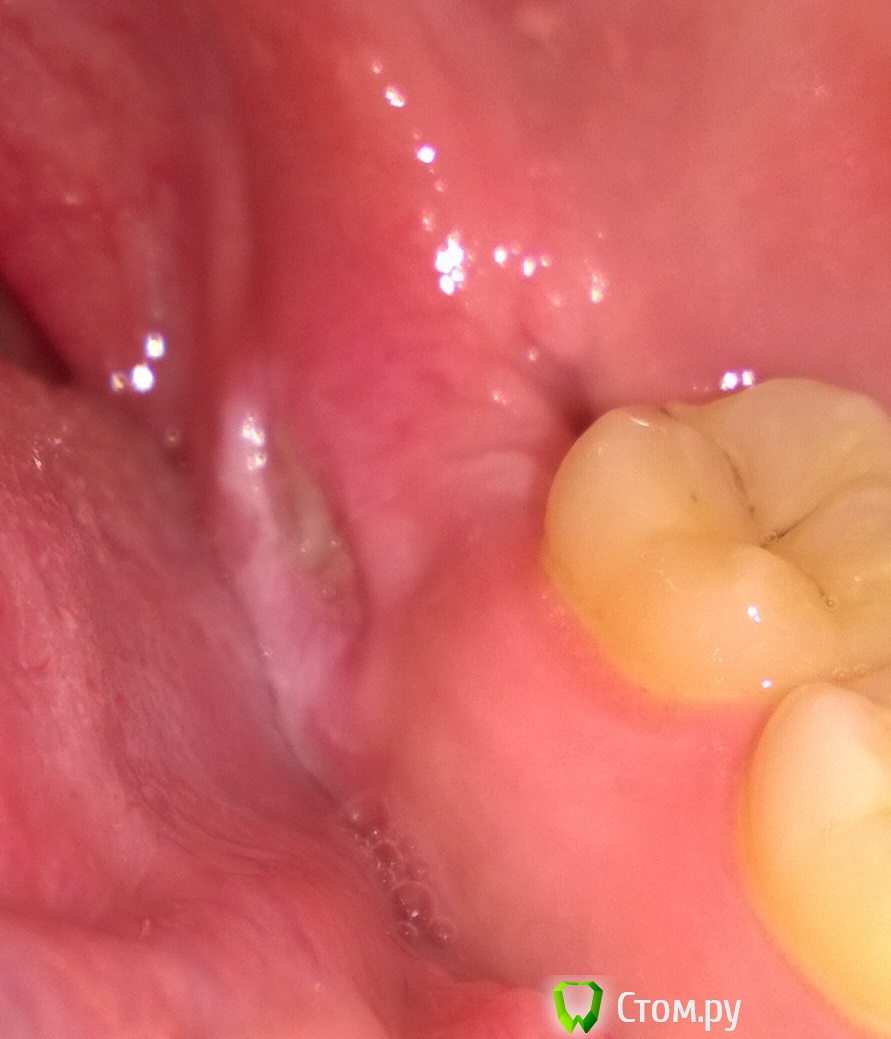

888 Опубликовано 24 февраля, 2014 Автор Поделиться Опубликовано 24 февраля, 2014 Откопал свою тему :-) Две недели назад удалил нижнюю слева, снова все без проблем, тот же врач. Только вот на прошлой неделе обнаружил (как я потом уже узнал от хирурга) под десной со стороны языка альвеолярные края, он сделал махинации в виде надрезов, фрезой сгладил, пощупал пальцем, но вот тут начинается самое интересное: почему то не стал зашивать. Намазал солкосерилом и сказал мазать это место так неделю-две. Вот прошла неделя, рана претерпела изменения, сгустка нет, просто белая сверху. Моё параноидальное сознание думает что это виднеется кость. Размер 3х6мм примерно, болей нет. Был у него сегодня, сказал продолжать мазать. Подскажите что это? Если нужны фотографии - изловчусь. Ссылка на комментарий

888 Опубликовано 25 февраля, 2014 Автор Поделиться Опубликовано 25 февраля, 2014 Ждем фото Цвет от вспышки исказился) Ссылка на комментарий

IvanK Опубликовано 25 февраля, 2014 Поделиться Опубликовано 25 февраля, 2014 лунка выглядит не плохо. Заживет)) 1 Ссылка на комментарий

Bier Опубликовано 25 февраля, 2014 Поделиться Опубликовано 25 февраля, 2014 Можно спилить этот участок, заживет быстрее 2 Ссылка на комментарий